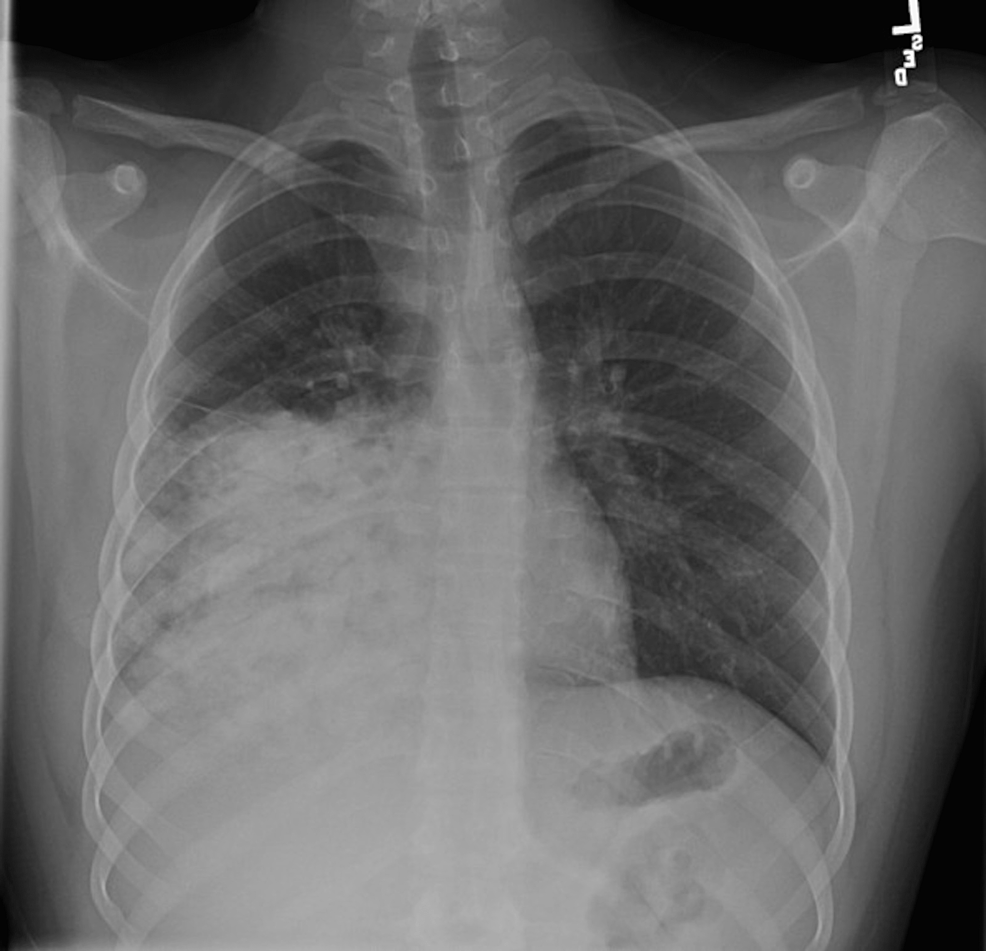

This case report highlights the importance of a detailed travel history and the need to revisit the differential diagnosis when there is an unexpected clinical course. A previously healthy 15-year-old...

Blastomycosis is caused by a dimorphic fungus endemic in certain parts of the United States including areas surrounding the Mississippi and Ohio River valleys, some southeastern states, and areas bordering the Great Lakes. Autochthonous blastomycosis is not seen in Florida. The infection is acquired by inhalation of the organism and is...